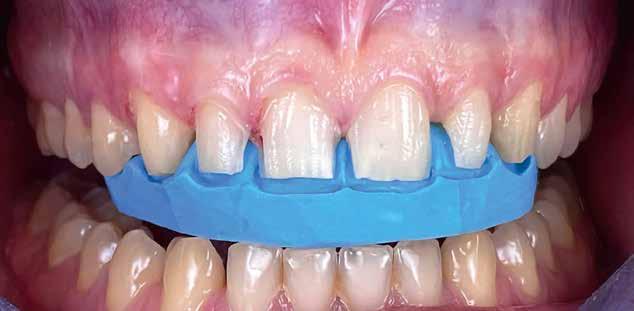

A kezelőorvosnak lehetősége van ezzel a labor számára kiegészítő információk közlésére, amelyek IOS-rendszerben nem lehetségesek – pl. középvonal, ajaktelítettség, mosolyvonal (20-21. képek)